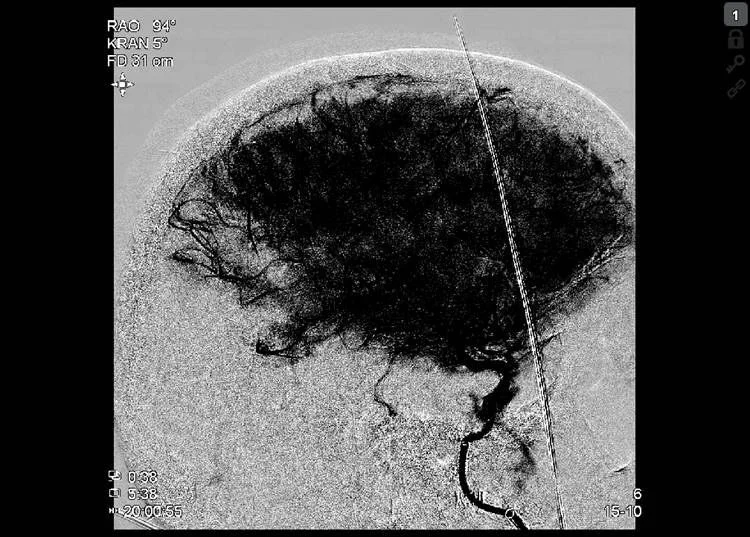

Thrombectomy was done with Embovac and Tigertriever (Rapid Medical) in general anaesthesia (door-to-groin 109 min, 19:44) with first pass recanalization TICI 2c in 16 min (20:00, door-to-final-TICI 123 min).